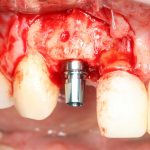

Установка имплантатов.

Напомню, что для этой работы я выбрал субкрестальные имплантаты Ankylos C/X. Они прекрасно сочетаются с любым методом остеопластики.

Я не планирую установку супраструктур или коронок, поэтому на уровень первичной стабильности можно положить болт. Даже наоборот — чем меньше крутящий момент при установке, тем лучше. Для имплантатов Ankylos и подобных им, это особенно важно. В общем, момент силы при установке — не более 10-15 Нсм.

Ремарка: имплантаты с предустановленными имплантодержателями хороши тем, что с ними легко контролировать позиционирование имплантатов. В случае с Ankylos С/Х - еще и крутящий момент. Имплантодержатель должен отсоединяться от имплантата с легким щелчком. Если его клинит, и тебе приходится прикладывать для этого усилия, то ты, однозначно, превысил момент силы во время установки имплантата. Следовательно, жди проблем.

Глянем на то, что получилось: